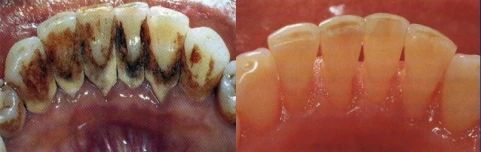

治療前/治療后

有一名女士,刷牙時經常牙齦出血,有時候輕輕咬一口蘋果,也會殘留血跡,這讓她十分擔憂口腔健康狀況,遂于近日來我院口腔科就診。

口腔科主任、副主任醫師侯少慧接診,通過全面細致的口腔檢查,結合臨床經驗,確診為牙周炎。經過一系列牙周治療后,患者牙齦出血得以顯著改善。“沒想到,在口腔科治療以后,現在刷牙時再也不像以前那樣總是出血了,真的很感謝醫生。”她高興地說。